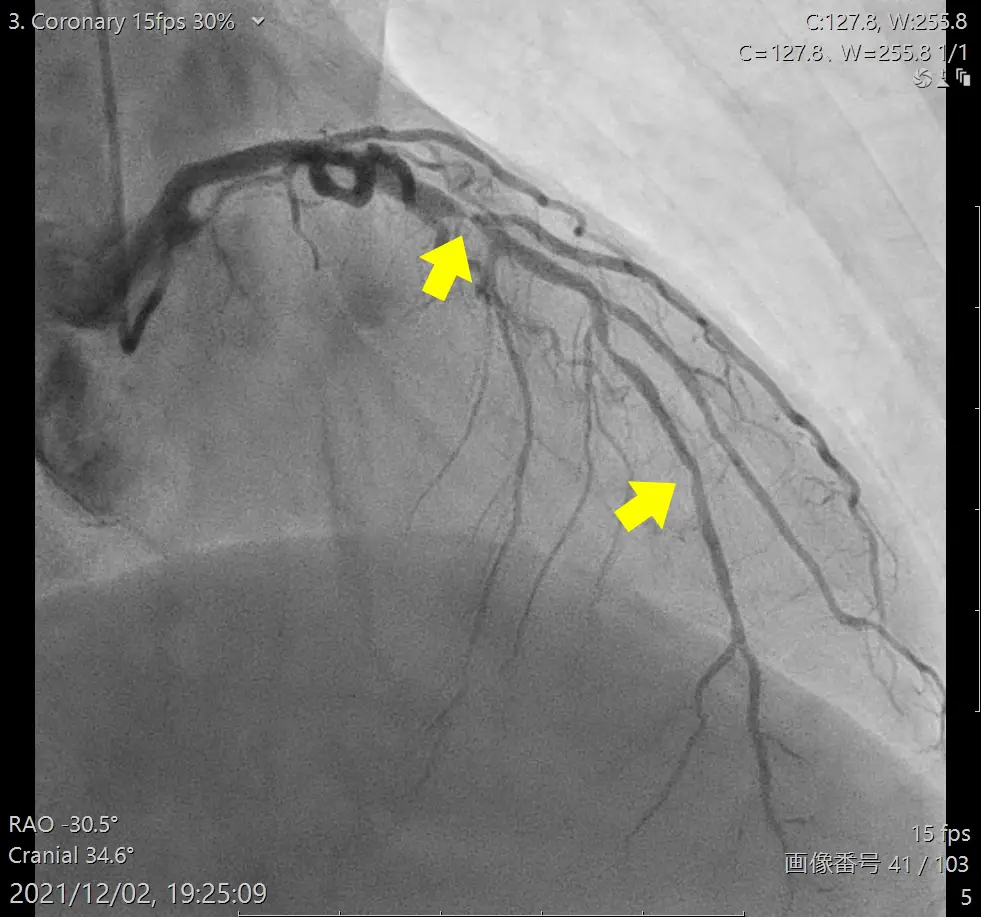

- カテーテル造影検査

造影剤を点滴したうえでCTで冠動脈を撮影します。血管の狭窄箇所(狭くなっている部分)や石灰化の有無を調べます。狭心症の検査では一番重要と言えます。比較的短時間で済み、体への負担が少ない検査です。ただし、造影剤にアレルギーがある方や腎機能が低下している方は注意が必要です。

カテーテルといわれる細い管を使用して、足の付け根などから血管を通じて心臓にアプローチする経皮的冠動脈形成術(PCI)と呼ばれる治療です。実際の手技としては、プラークにより狭くなっている箇所をバルーンで広げたうえで、再度の狭窄が起こらないようにステントと言う特殊な金属でできたメッシュ状の管を留置します。胸を開かず、人工心肺も利用しないため、体への負担が軽く(低侵襲)、入院期間を短縮できるのが特長です。当院での治療は最短だと1泊2日で行っています。お仕事をされている方の場合、退院翌日には就業が可能です。